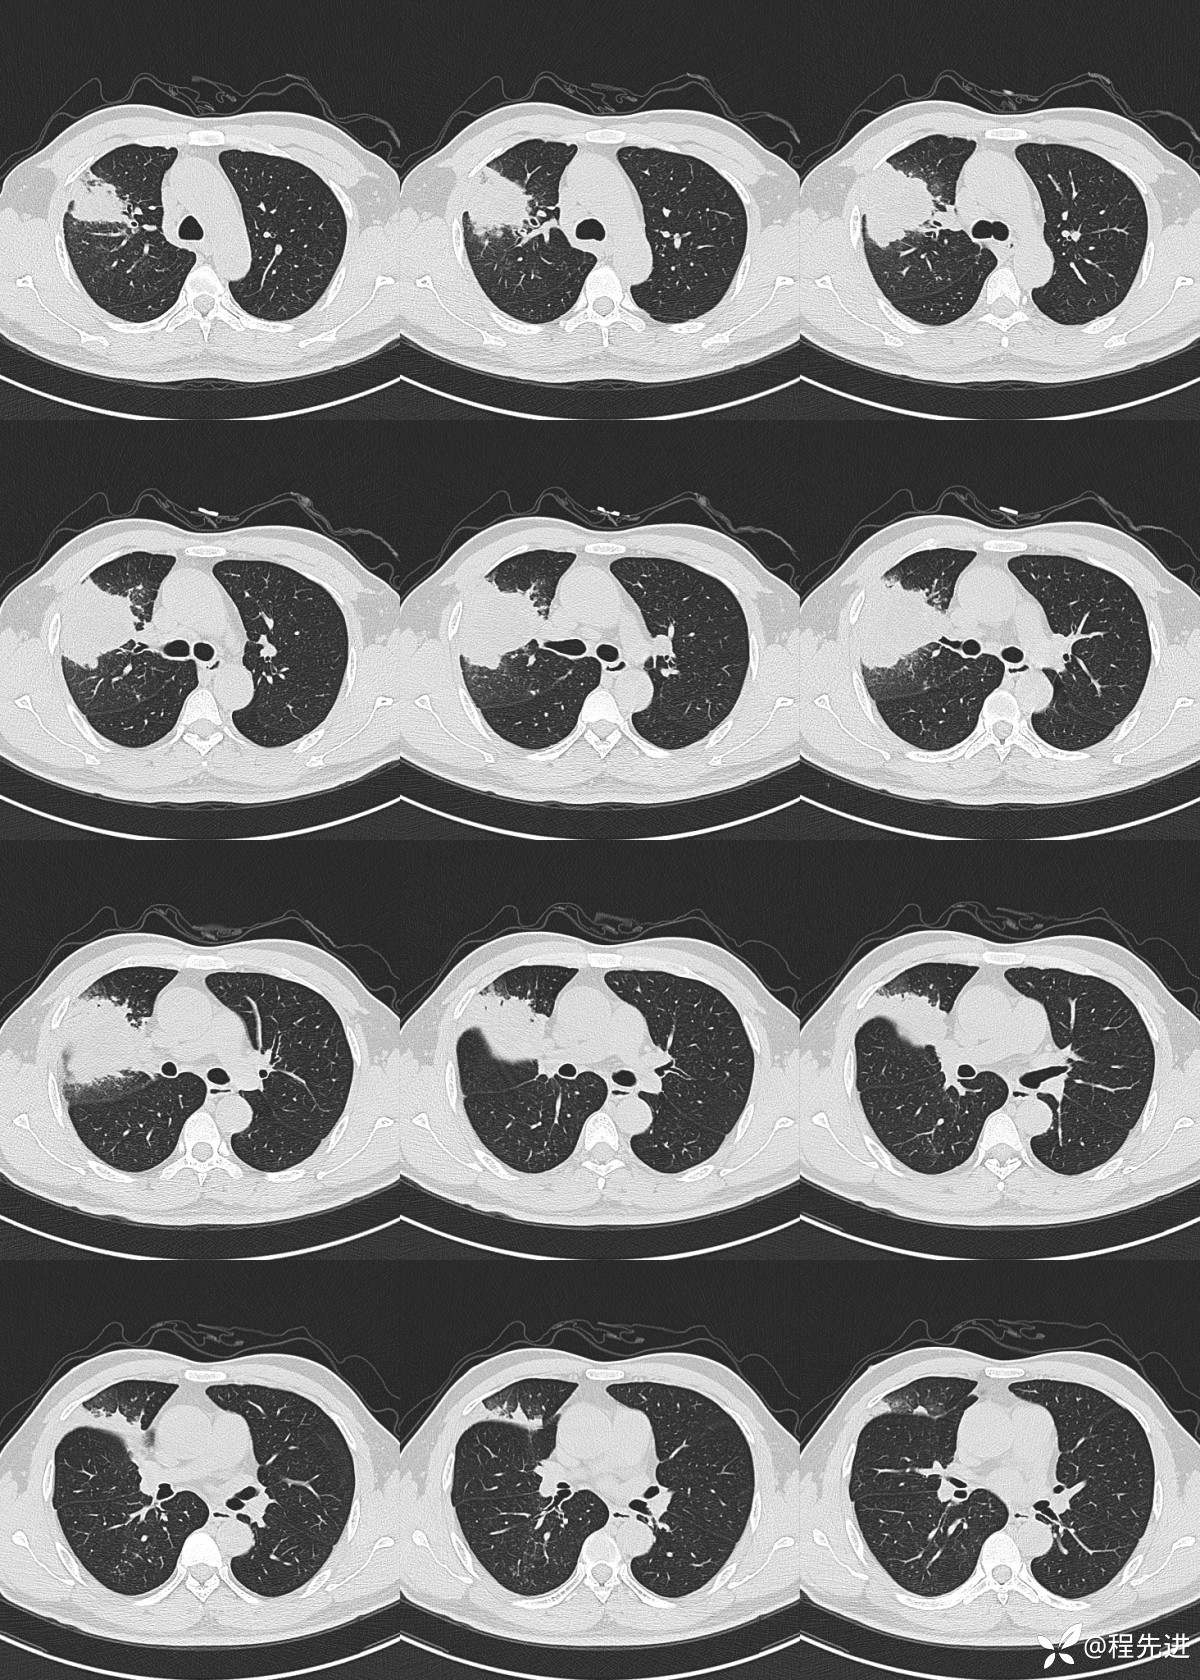

肺窗:(薄层图像,只挑了几个典型层面,但层面不连续)